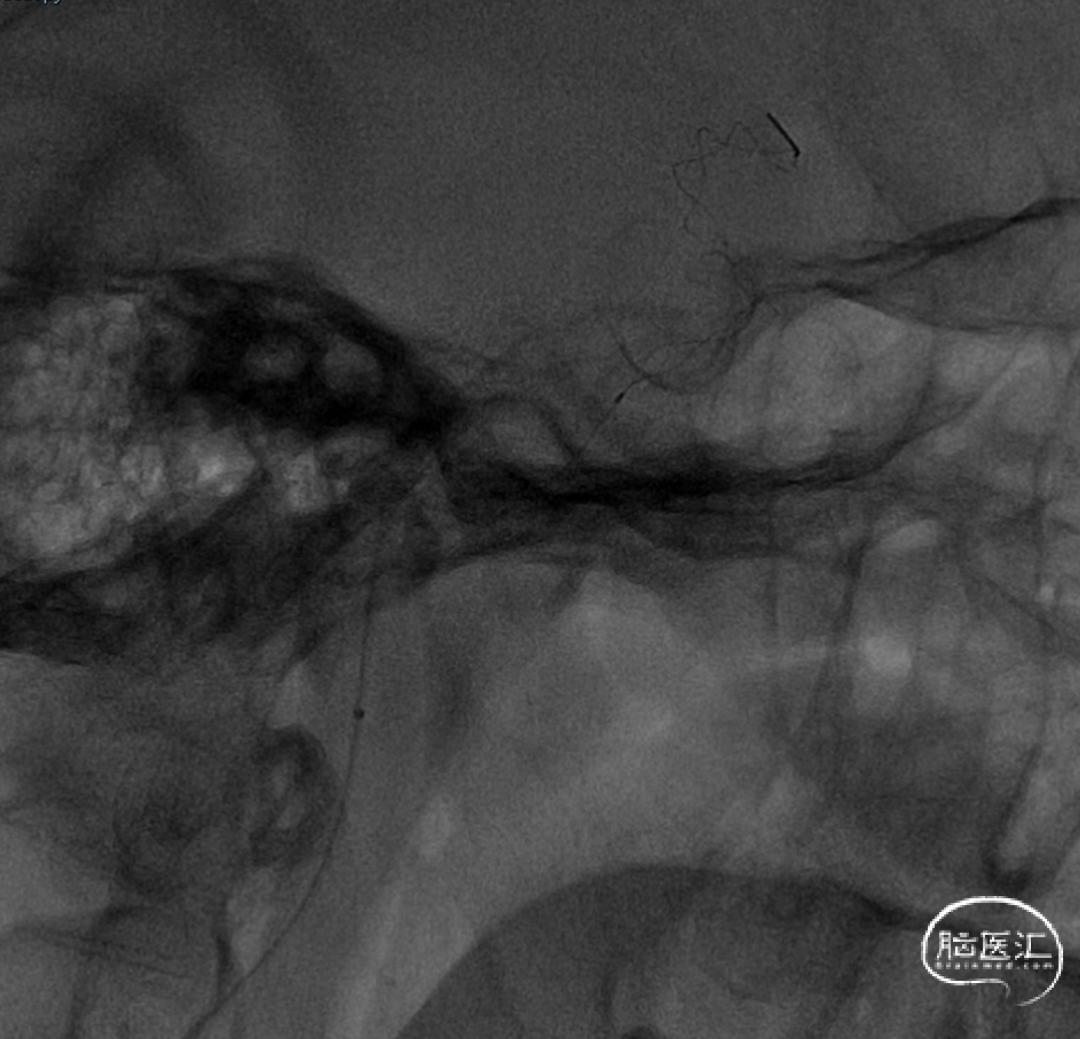

前送5F Tethys®中间导引导管至大脑中动脉M1段,在负压抽吸下将Syphonet®取栓支架回收至中间导管内,并缓慢回撤Tethys®中间导引导管至C5段,持续负压下将Syphonet®取栓支架撤出,抽吸注射器内无明显血栓,支架上可见1mm血栓碎片,术中观察患者意识、肢体功能较前无明显变化。

保护伞装置下,处理C1段狭窄:

· 沿5F Tethys®中间导引导管送入3.5-5.5mm×300cm 保护伞于C5段释放,同轴送入Sterling 4.0mm×30mm 球囊扩张导管并覆盖C1段最狭窄处理,以14atm扩张维持约5秒并迅速释压,观察约1分钟患者心率及血压无明显变化,且意识及肢体功能无明显改变,复查造影示C1段狭窄较前明显改善。

· 撤出球囊导管送入7.0×40mm 自膨式支架,在路图及造影下定位,于狭窄处释放,再次造影提示C1段残余狭窄<10%,保护伞处近端造影剂充盈欠佳。